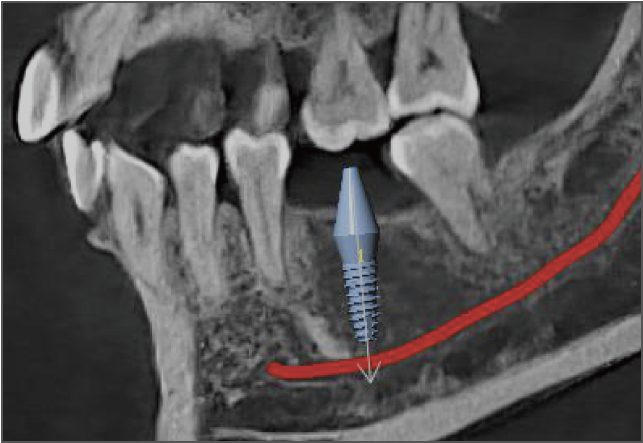

• lamtau AI神經管標記

AI神經管標記

• lamtau 模擬種植

模擬種植